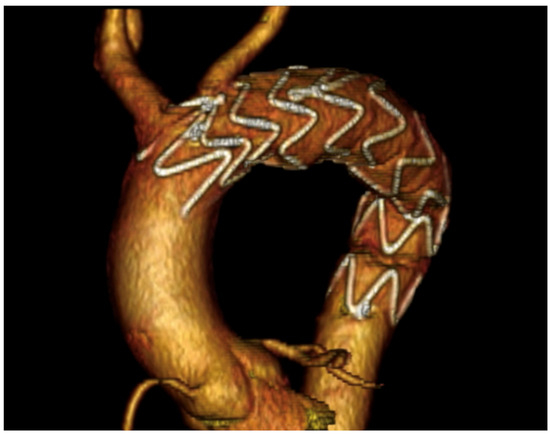

| Current Case-2 | 46 | M | Aortic arch | Asymptomatic | 21 years | Hybrid (carotid-subclavian bypass + TEVAR) |